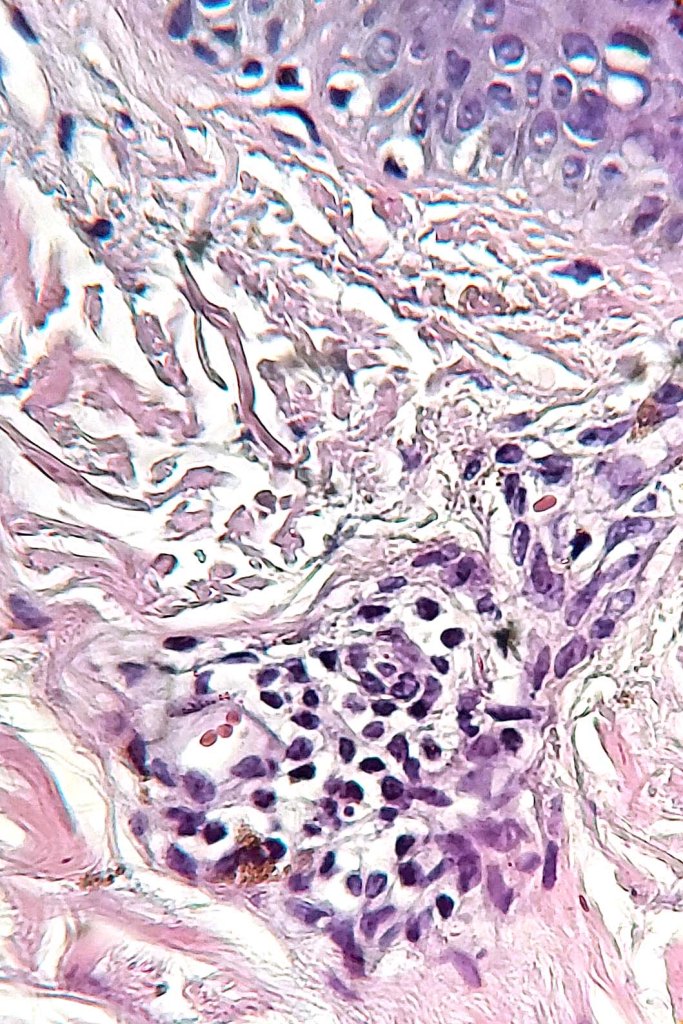

Histologically, both lesions are characterized by the presence of denritic melanocytes in the upper & mid dermis. The overlying epidermis is often hperpigmented and increased numbers of melanocytes are sometimes evident.

Histologically, it is characterized by a dense population of spindled, dendritic melnanocytes & melanophages with variable fibrosis. It may sometimes represent a component of a combined nevus. Mitotic activity is not usually present and pleomorphism is absent (see atypical blue nevus below). Involvement of the arrector pili muscle is not uncommon.